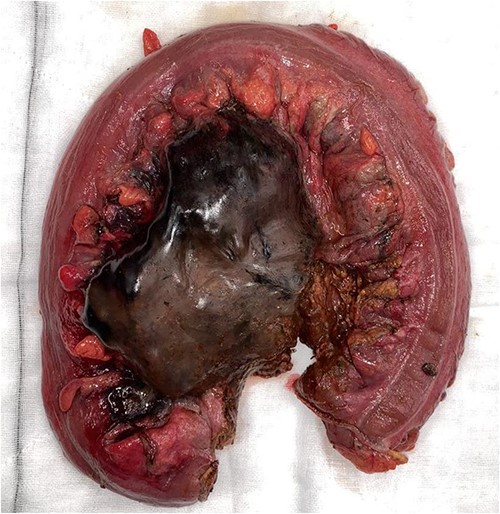

Resected specimen demonstrating ischaemic necrosis and faecaloma through large stercoral perforation.

Histopathology confirmed the presence of a full thickness perforation approximately 50 mm in length, with surrounding ischaemic necrosis of the mucosa and a massive faecaloma, confirming the diagnosis of stercoral perforation associated with ischaemia. Although there have been limited case reports of stercoral perforation described in schizophrenic patients requiring Clozapine and other antipsychotics that have a constipating effect [6, 10], Ms IW had been on long-term Clozapine and her stercoral perforation was believed to be associated with her comorbidities and adjuvant chemotherapy, not just associated with Clozapine.